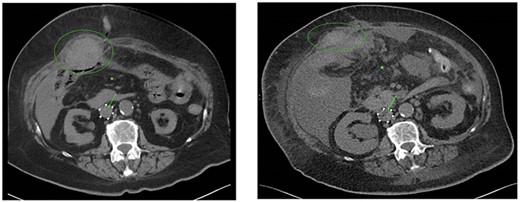

A 64-year-old female was diagnosed with a left-sided cT2N1M0 lobular breast carcinoma for which she was treated with neoadjuvant chemotherapy. Partial radiological response was observed (Fig. 1) and an oncoplastic breast-conserving surgery was performed. After pathological examination, an ypT2N1a(sn) TNM classification (8th edition UICC), ER-positive (100%), PR-negative (0%) and HER2-negative, was found, and adjuvant radiotherapy and hormone therapy were indicated.

(A) Axial slice of a thoracic PET/CT showing the lobular carcinoma in the left mamma (green arrow) before neoadjuvant chemotherapy. This PET/CT was performed 7 months prior to ER presentation. (B) Axial slice of a thoracic PET/CT showing the lobular carcinoma in the left mamma (green arrow) after neoadjuvant chemotherapy with partial response. This PET/CT was performed 7 weeks prior to ER presentation.